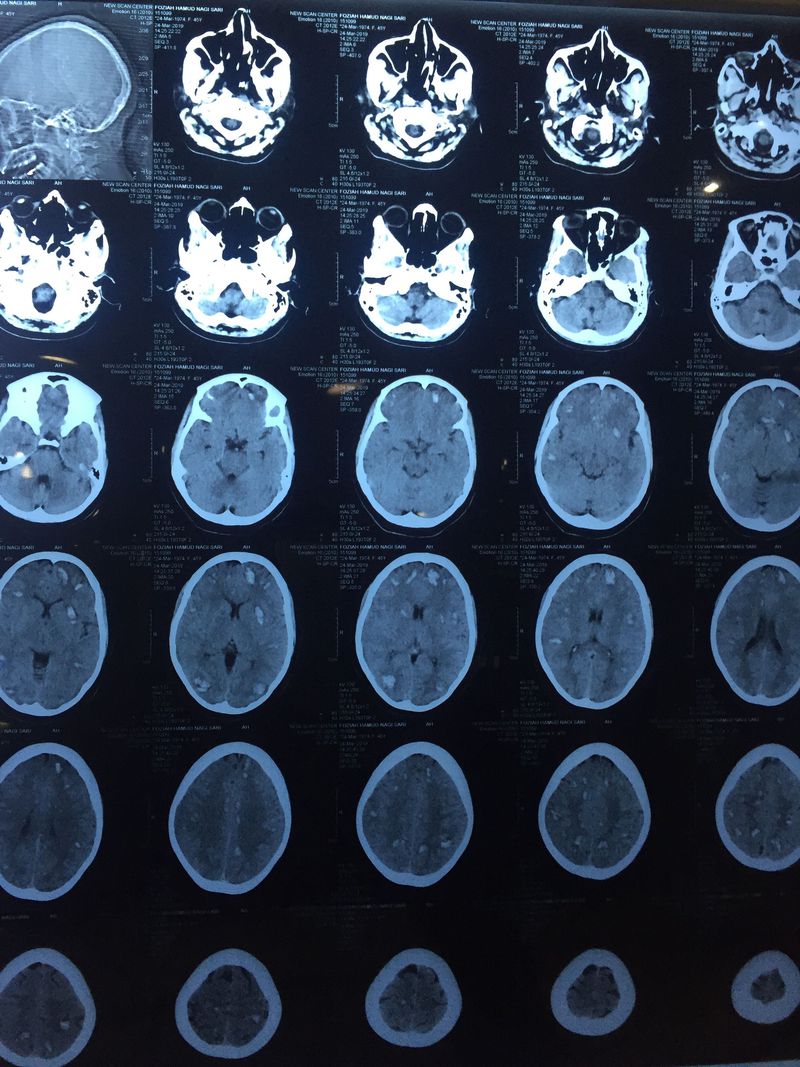

Multiple brain haematoma

24 years old female was pregnant in 16 weeks had severe watery diarrhea then pass in acute renal impairment had tow sets of HD Then she passed in coma She aborted before the HD suddenly What are the DD of this case

What caused the brain hematomas?? Was this a cancer of some type?

Immune thrombocytopenic purpura, hemolytic uremic syndrome